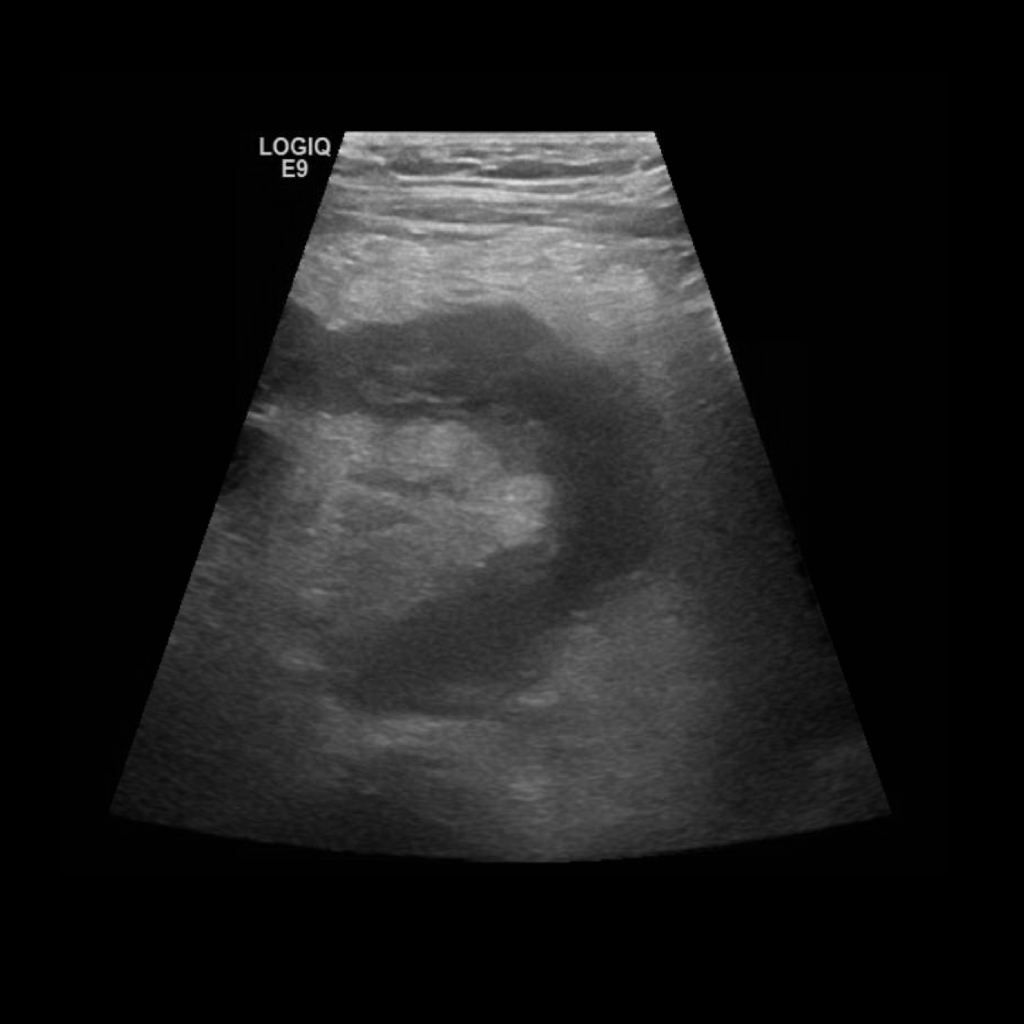

Appendicitis 2

Large appendix with appendicolith and hyperemia.